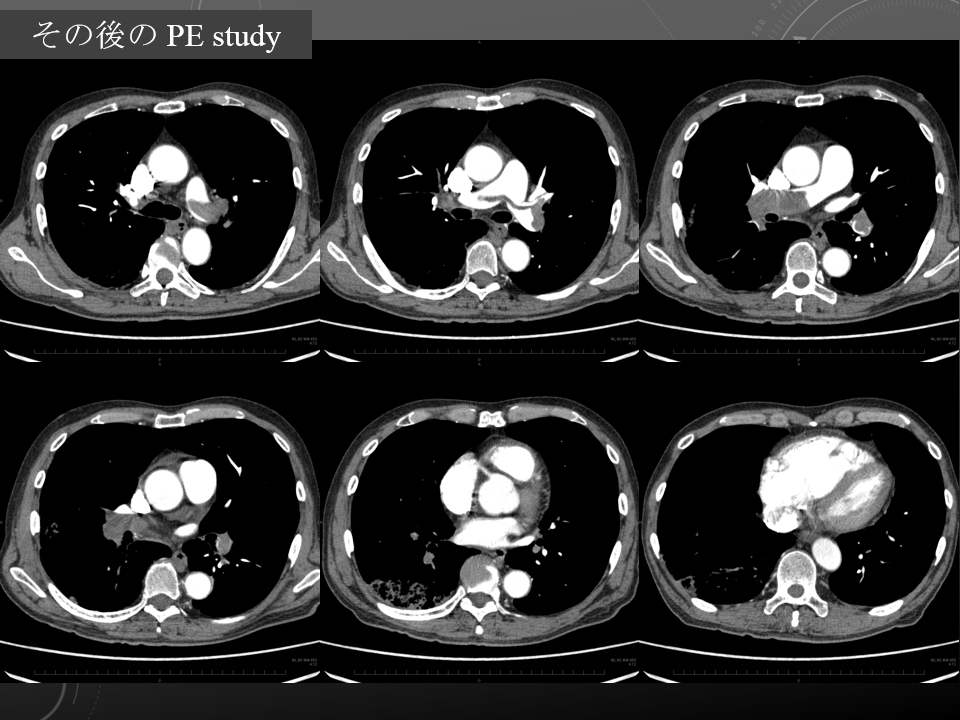

厳密には PE study が行われたのは翌日

2週間前犬の散歩中に突然の呼吸苦、乾性咳嗽出現。近医受診、鎮咳薬で経過観察。この際不整脈(?)を指摘。その後も乾性咳嗽が持続するため当院受診。外来待合室で呼吸苦出現。SpO2 77% (ambient air)。

右心系の拡大もあるのか…

右心系の拡大もあるのかも。。。